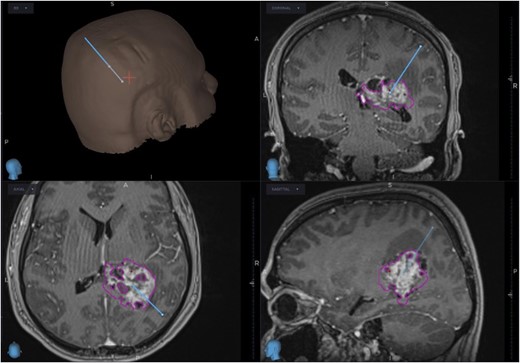

The patient was started on oral dexamethasone, resulting in the improvement of his headaches. The differential diagnosis based on imaging findings included an atypical meningioma, central neurocytoma, choroid plexus papilloma or carcinoma, ependymoma or an oligodendroglioma. He underwent a right parietal craniotomy with gross total resection of the lesion. Intraoperatively, use of the Vycor™ ViewSite Brain Access System (VBAS) was utilized, which allowed for optimized surgical site access, and reduced the risk of brain retractor injury to surrounding structures, namely the precentral gyrus. This was combined with intraoperative ultrasound (Fig. 3), which provided real time imaging and guided the extent of the resection. In addition, neuromonitoring and neuronavigation (Fig. 2) were incorporated to further reduce the risk of damage to surrounding structures. As part of the neuromonitoring, motor evoked potentials (MEPs) were performed to identify the precentral gyrus prior to insertion of the VBAS (Fig. 4), ensuring that any resection occurred posterior to the motor strip. During surgery, it was noted that the lesion was haemorrhagic and easily friable, with evidence of a previous recent haemorrhage.

Preoperative (5a) ultrasound images depicting a heterogenous mass with hyperechoic and hypoechoic regions. Post-operatively (5b), a hyperechoic region is noted; however, no distinct lesion is identified.